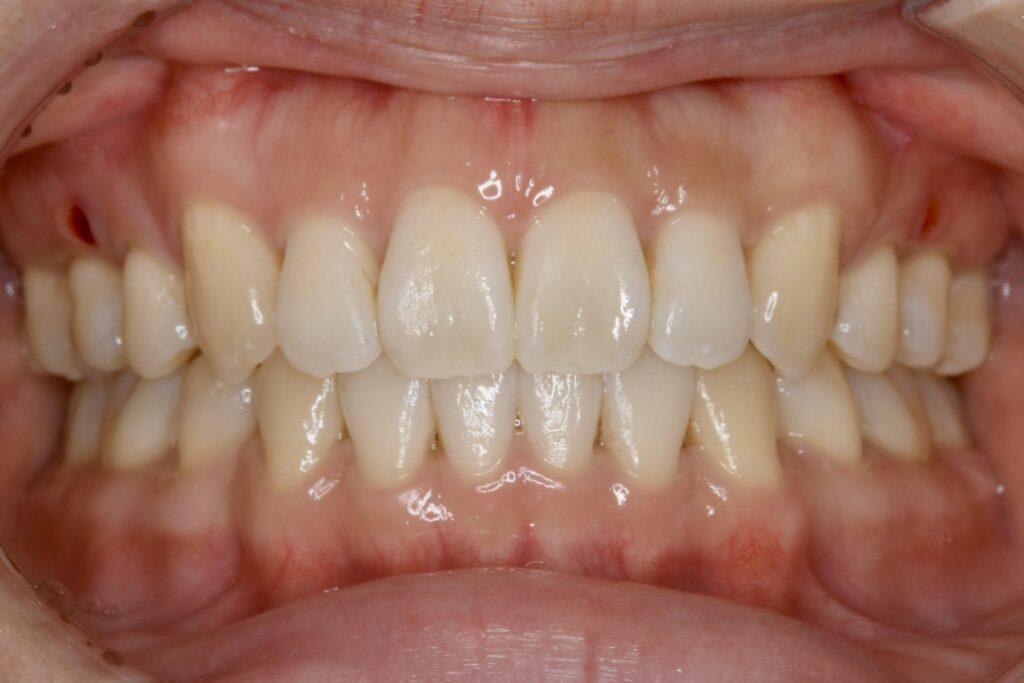

| 主訴 | 写真を見て歯並びが気になる。特に下の前歯はガタガタが強く治したい。 |

|---|---|

| 診断名・主な症状 | 叢生 |

| 年齢 | 19歳 |

| 治療内容 | 上下とも歯並びの幅を広げることでできたスペースを利用して、ガタガタを解消しました。 |

| 使用装置 | 表側矯正(ワイヤー) 矯正用ミニインプラント |

| 抜歯部位 | 抜歯なし |

| 治療期間 | 1年10ヶ月 |

| 通院回数 | 25回 |

| 費用 | 91万円程度(税別) 220 |

| リスク・副作用 | 痛み、歯肉退縮、歯根吸収、抜歯に伴う出血や腫れが生じることがあります。 |